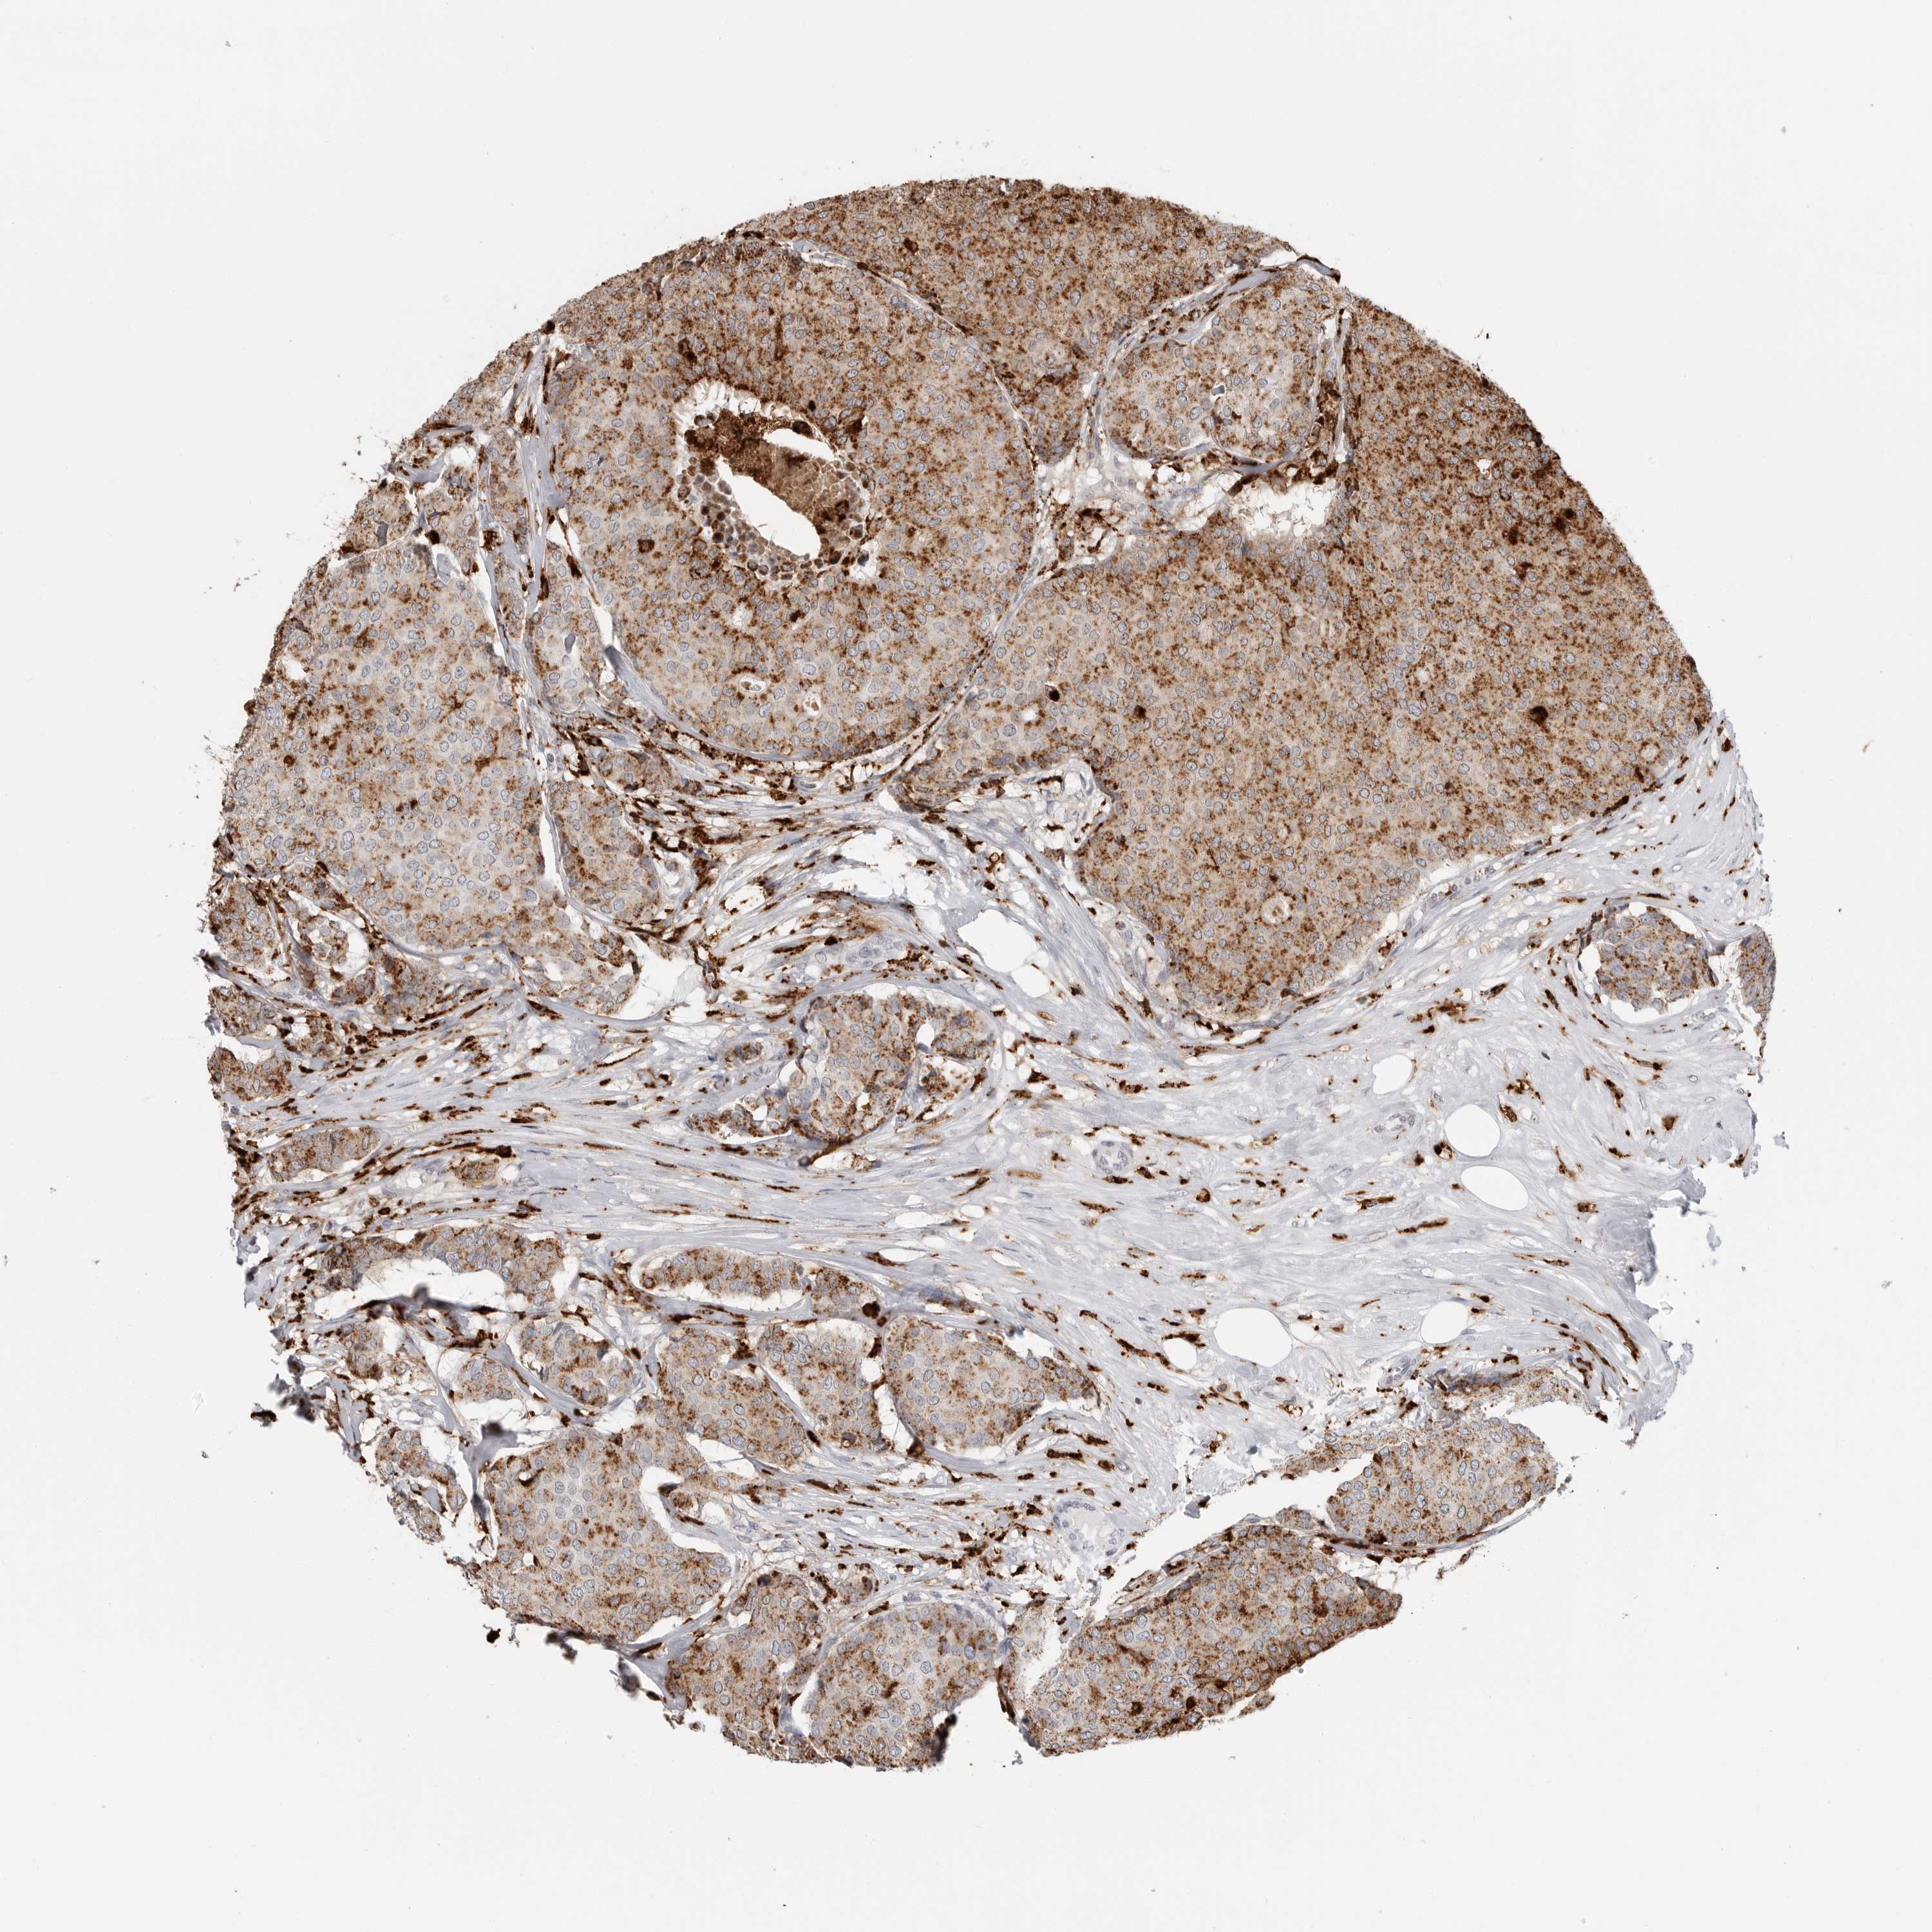

CANCER BREAST CANCER Show tissue menu

Breast cancer

Human cancer